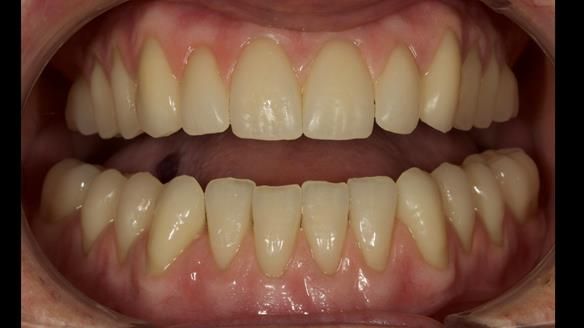

This newsletter describes in step by step detail the provision of a lower implant supported metal based complete denture with three dental implants positioned in the anterior mandible. The upper arch was restored with a metal based complete upper denture.

This 72 year old woman (Mary) was referred to me from her general dental practitioner from Ireland.

Mary had 3 dental implants placed in the anterior mandible 10 years previously with new complete dentures. These were successful for a time. The dentures were replaced a few years later. Mary was never pleased with the new lower denture as they did not fit the implants properly. This patient was referred to me from Ireland, to my practice in Garstang, England.

Diagnoses of the complete dentures

- Locator attachments not engaging the housings in the lower denture.

- Suboptimally shaped dentures with poor tissue fit resulting in rocking of the dentures.

- Bland aesthetics.

I provided new metal based complete dentures. The clinical situation and treatment process is shown in detail below with photographs. I provided the clinical work and Rowan Garstang provided the technical work. The dentures took 5 visits to make - with the patient travelling by plane from Ireland to Manchester. The patient had one review after the dentures were fitting.